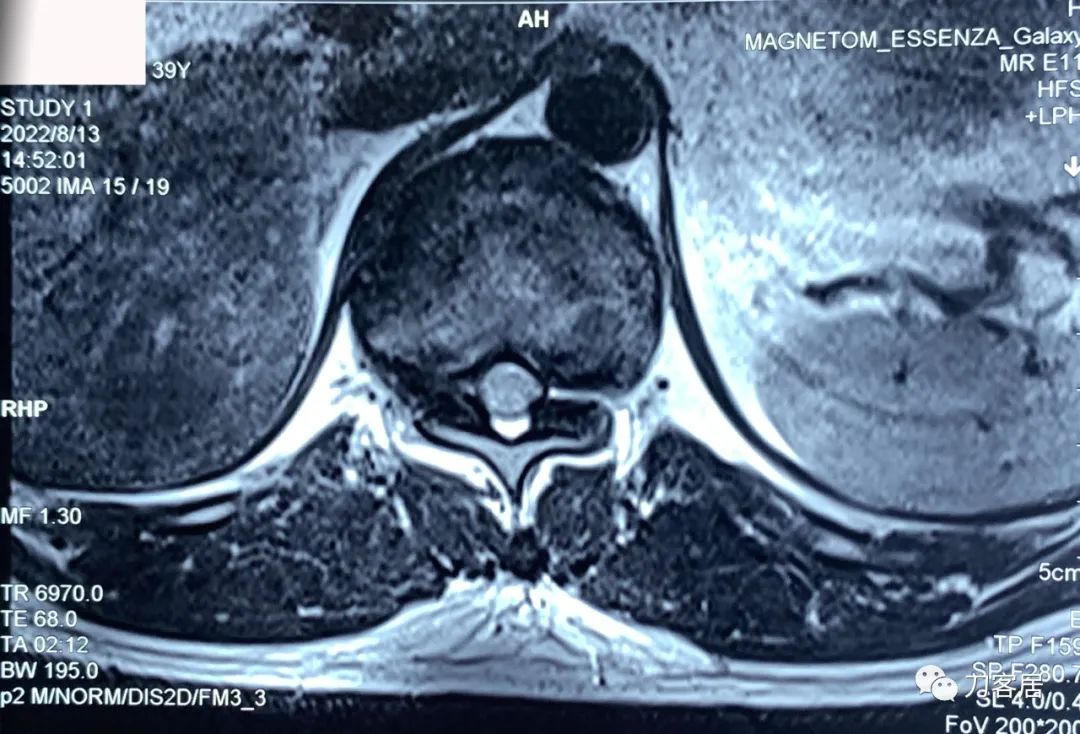

图7. 20220813西安第三方影像机构胸椎MRI01,提示胸8-9椎间盘突出,胸11-12椎间盘突出,椎管狭窄。

图8. 20220813西安第三方影像机构胸椎MRI02,提示胸8-9椎间盘突出,胸11-12椎间盘突出,椎管狭窄。

图10. 20220813西安第三方影像机构胸椎MRI04,提示右侧隐窝狭窄,右侧黄韧带肥厚,但椎管狭窄并不那么严重。

图11. 20220813西安第三方影像机构胸椎MRI05,显示两侧胸椎黄韧带肥厚,右侧明显。但脊髓压迫似乎并不那么严重。

图12. 20220813西安第三方影像机构胸椎MRI06,显示两侧胸椎黄韧带肥厚,右侧明显。但脊髓压迫似乎并不那么严重。